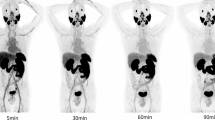

The biodistribution of 67Ga-DOTA-(D-Asp)n (nā=ā2, 5, 8, 11, or 14), 67Ga-DOTA-(L-Glu)14, 67Ga-DOTA-(D-Glu)14, [18F]NaF, and 99mTc-MDP in normal mice is shown in TablesĀ 1ā9. Among these compounds, 67Ga-DOTA-(D-Asp)8, 67Ga-DOTA-(D-Asp)11, 67Ga-DOTA-(D-Asp)14, 67Ga-DOTA-(L-Glu)14, 67Ga-DOTA-(D-Glu)14, [18F]NaF, and 99mTc-MDP showed high accumulation and retention of radioactivity in bone. 67Ga-DOTA-(D-Asp)5 showed moderate accumulation of radioactivity in bone; however, the level of radioactivity decreased 3āh after injection. 67Ga-DOTA-(D-Asp)2 caused subtle accumulation of radioactivity in bone. Although there was little radioactivity in other tissues at 3āh after the injection of 67Ga-DOTA-(D-Asp)n, 99mTc-MDP, and [18F]NaF because of rapid excretion via the kidneys, the radioactivity in the kidneys after the injection of 67Ga-DOTA-(L-Glu)14 and 67Ga-DOTA-(D-Glu)14 was retained.

To compare the biodistributions of 67Ga-DOTA-conjugated acidic amino acid peptides with the biodistributions of other typical bone-seeking compounds, biodistribution experiments of 99mTc-MDP and [18F]NaF were performed. 67Ga-DOTA-(D-Asp)11, 67Ga-DOTA-(D-Asp)14, 99mTc-MDP, and [18F]NaF showed excellent biodistribution as bone imaging agents, such as high bone accumulation and low radioactivity in non-target tissues. Among these agents, as [18F]NaF showed the highest bone uptake, [18F]NaF may have the most preferable biodistribution as a bone imaging agent. However, the bone/non-target tissue radioactivity ratios of 99mTc-MDP and 67Ga-DOTA-(D-Asp)n (nā=ā11 or 14) are sufficient for bone imaging, and 99mTc and 68Ga have some convenient physical properties as radionuclides. Thus, 99mTc-MDP and 68Ga-DOTA-(D-Asp)n (nā=ā11 or 14) should be useful in a clinical context.